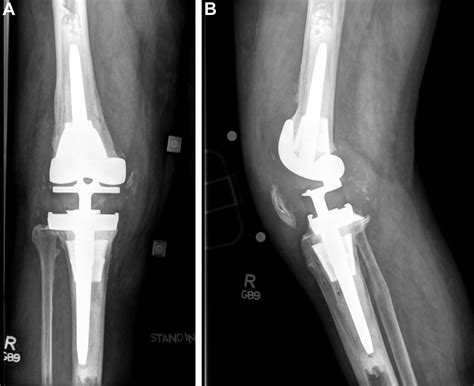

Here is an example of knee replacement images that illustrate the surgical procedure:

Knee Replacement Procedure

📸 Note: The images above are for illustrative purposes only. Always consult with a healthcare provider for personalized information.